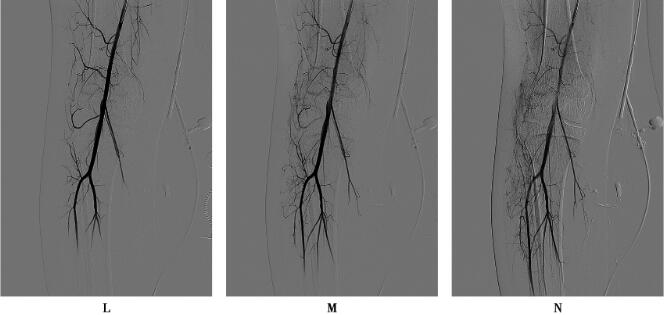

DSA经皮超选择性动脉造影:右膝、胫骨外侧动脉期可见增粗胫前动脉分支供血,动脉中末期上述部位可见畸形血管团,引流静脉进入腘、股静脉,证实为动静脉畸形,向畸形血管团内注入1.5ml无水酒精+0.5mPVA+博来霉素混合液行畸形血管栓塞治疗。

右侧膝关节、胫骨外侧软组织内动静脉畸形(AVM)。

动静脉畸形(AVM)是一种先天性发育异常,源于胚胎第4~8周局部血管异常分化,占血管瘤和血管畸形1.5%,男女比例为1∶1.5,可发生于身体任何部位,以中枢神经系统、头颈部、骨盆和下肢更常见,通常出生即存在,随身体发育同步缓慢生长,可长期稳定,也可突然迅速增大。在诊断上,普通CT或MRI平扫加增强扫描显示病灶为软组织肿块,缺乏特异性,难以与其他软组织肿瘤或肿瘤样病变鉴别,确诊依赖血管造影检查。DSA能准确显示AVM异常血管团的范围、供血动脉、引流静脉等信息,清晰显示各级血管及动静脉的异况,并能动态显示病灶血流动力学特点,空间和时间分辨力均高,还可同步进行血管内治疗,长期被认为仍是诊断AVM的“金标准”,但是DSA属于创伤性检查,X线辐射剂量较高、检查费高、不能显示病灶与周围组织的关系等诸多缺陷,逐渐被无创伤的血管成像所替代。其中CE-MRA是一种相对简便易行、无创伤、无射线辐射危害、价格相对便宜的诊断方法,当对比剂首次通过靶血管区,在峰值的一段时间内,从三维方向快速采集感兴趣区的图像数据,并通过各种后处理技术最终产生类似DSA的效果,并可获得多角度投影的CEMRA图像,CE-MRA可客观、准确评价下肢血管情况,清晰显示病灶范围及与周围软组织关系,并能区分不同类型血管畸形。AVM难以治愈,在治疗上,外科手术难度大,术后容易复发,目前倾向于多学科联合治疗,其中介入栓塞治疗是重要的治疗手段。本例病变位于右下肢软组织内,MRI平扫和增强扫描显示软组织肿块,缺乏诊断特异性,难以与各软组织良恶性肿瘤鉴别,CE-MRA显示典型的异常血管团、供血动脉和引流静脉,确定AVM的诊断,DSA进一步证实诊断并实施介入栓塞术。